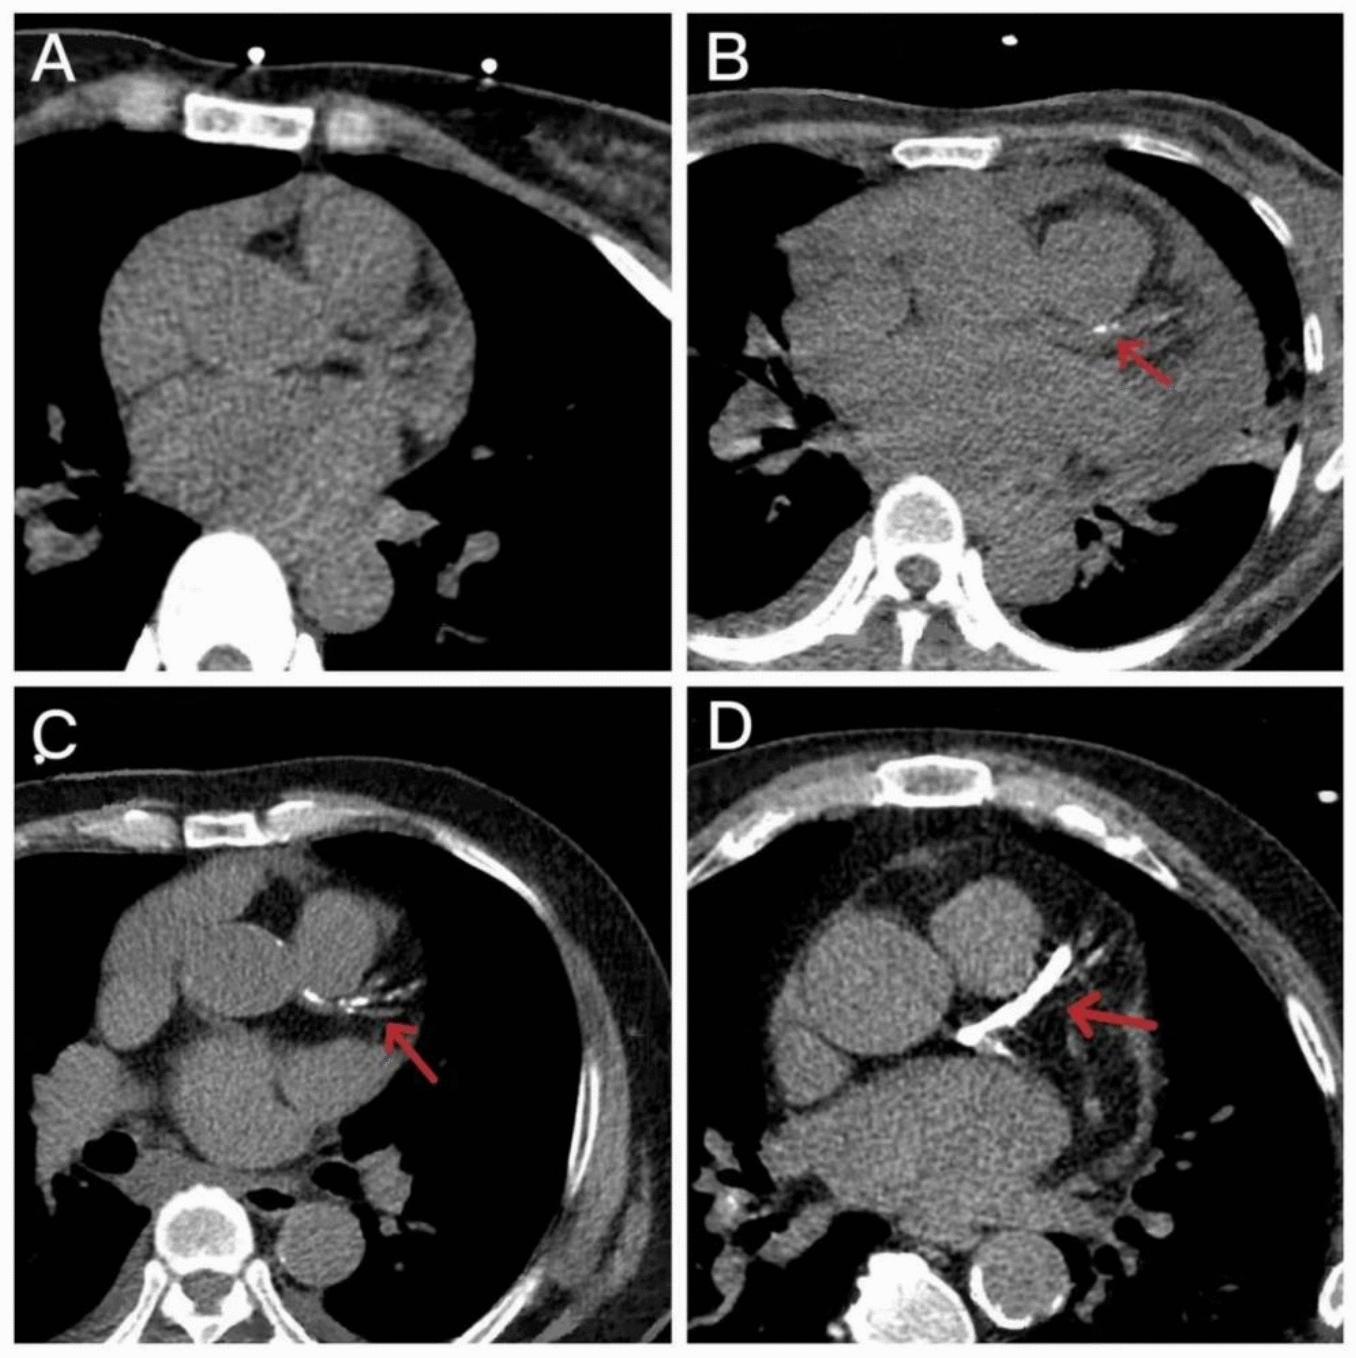

This study selected 86 patients who initiated in-center MHD between March 2021 and November 2022. Demographic characteristics, medical history, and laboratory data were collected. Coronary artery calcification (CAC) was assessed based on the Agatston vascular score determined via computed tomography. Serum levels of the VC inhibitors fetuin-A was quantified via enzyme-linked immunosorbent assays. Univariate and multivariate regression analyses were conducted to determine the risk factors for VC, and a neural network-based approach was adopted to construct a VC prediction model.

本研究选取了2021年3月至2022年11月期间开始进行中心MHD的86例患者。收集了人口统计学特征、病史和实验室数据。基于通过计算机断层扫描确定的阿加斯顿血管评分评估冠状动脉钙化(CAC)。通过酶联免疫吸附测定法定量血清中VC抑制剂胎球蛋白-A的水平。进行单因素和多因素回归分析以确定VC的危险因素,并采用基于神经网络的方法构建VC预测模型。